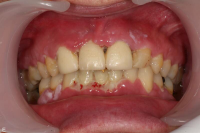

Gingivit är tandköttsinflammation som visar sig genom marginal blödning vid sondering, men där tanden ej har någon förlust av käkbensfäste.

Diagnosen gingivit används vid tänder med marginal inflammation och blödande tandkött, men ingen förekomst av marginal benförlust. Fickdjup 1–3 mm, pseudofickor kan förekomma upp till 5 mm.

Ödematös, rodnad och blödande gingiva.